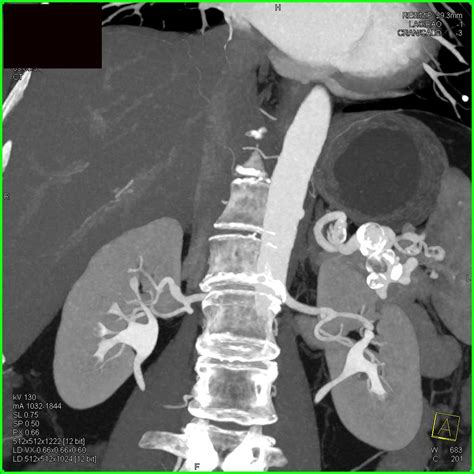

Angiography: Involves injecting a contrast dye into the blood vessels and taking X-ray images. It provides detailed images of the blood vessels and can help plan treatment.

Angiography is particularly useful for planning surgical or endovascular interventions.